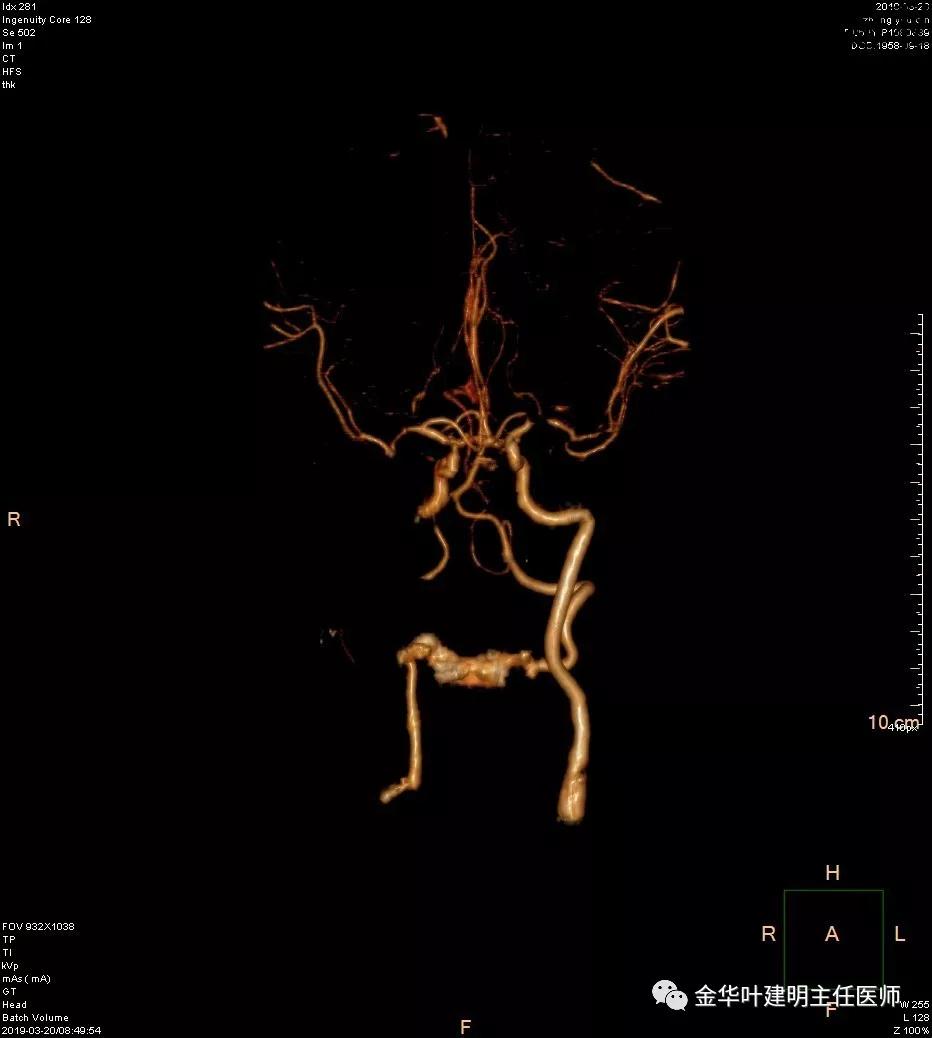

报告提示左侧大脑中动脉M1段及左侧大脑后动脉P1段管腔闭塞。按影像科的建议并请神经内科会诊后,予以行CTA检查。结果如下:

可见其左侧大脑中动脉起始部管腔重度狭窄,右侧大脑中动脉近段管腔也有狭窄;左侧大脑后动脉中远段未见显影。又建议其DSA检查。我们仔细询问章某平时没有神经系统的症状,回忆起来说大概3年前有段时间头昏比较明显,但也没有到大的医院详细检查,后来自行改善。鉴于平时并无明显症状,我们认为其脑血管的病变是慢性闭塞,并已经有侧支代偿。便先请神经外科会诊,会诊后的意见是可以先处理肺部疾病,待情况稳定后再到神经外科进一步诊治。这样,我们便打算为其进行手术。当然因为上叶病灶考虑良性,且位置靠肺外周部位,而下叶病灶考虑恶性,又是中肺叶中央,无法亚肺叶切除,况且病灶大于3厘米,密度虽还是混合磨玻璃,但已经明显偏向实性。所以拟定手术方式是“胸腔镜下左肺下叶切除+上叶楔形切除及纵隔淋巴结清扫术”,当然万一上叶也是恶性,也只能同样是这样的手术方式,全肺切除显然风险过高。